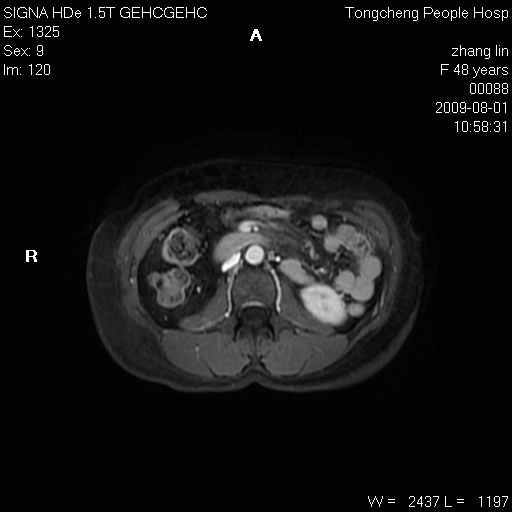

女,48岁。健康体检,彩超发现右肾占位性病变。平素健康。

临床诊断:右肾占位性病变,性质待定(囊肿?肿瘤?)。

上中腹部mr平扫+增强扫描,图像如下:

右肾上极见一类圆形病灶,t1wi呈等信号t2wi呈等高混杂信号,三期增强无强化,边界清---考虑囊肿出血。

同反相位均表现为等信号,病变无强化,考虑含蛋白的囊肿可能,弥散加权相或许有些帮助,